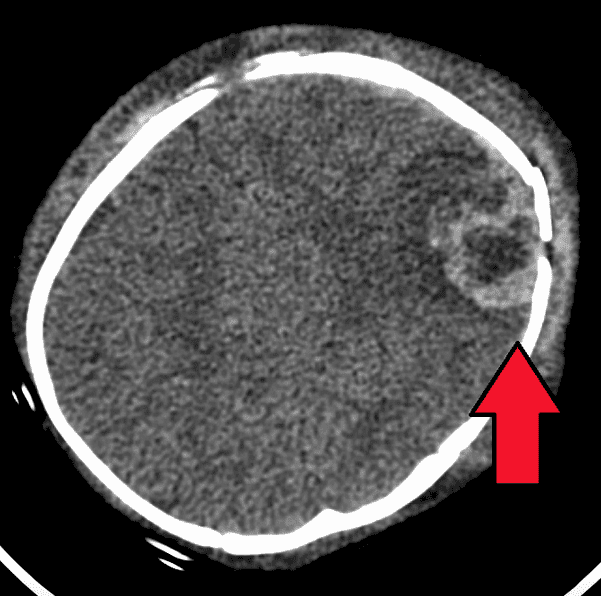

The history of medical interest in child abuse may have started in 1860, when Dr. Ambroise Tardieu, a French forensic physician, published a report on the physical maltreatment of children.3 This article produced little interest and did not stimulate further research or reports. After a dormant century, interest in childhood injuries started again in the second half of the twentieth century. Reports of infants with subdural hematomas (bleeding under the meninges covering the brain) and long bone fractures appeared in 1946 and 1950. The cause of the bleeding and the fractures was “not known.” Silverman4 in 1953 wrote that these fractures were “manifestations of unrecognized skeletal trauma.”

Kempe defined the battered child syndrome as a “clinical condition in young children who have received serious physical abuse and is a frequent cause of permanent injury or death.” The syndrome should be considered in a child with a bone fracture, subdural bleeding, failure-to-thrive (meaning lower than expected weight gain), swelling, bruising, sudden death, or where the history and the physical findings are discordant.